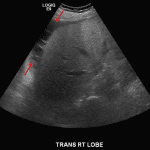

- Heterogeneous hypoechoic lesion in the periphery of the right hepatic lobe measuring up to 5.5 cm without internal vascularity

- Small volume, heterogeneous appearing perihepatic fluid

Heterogeneous hypoechoic lesion in the periphery of the right hepatic lobe measuring up to 5.5 cm without internal vascularity, concerning for an abscess. Adjacent small volume complex ascites raises concern for intraperitoneal rupture.